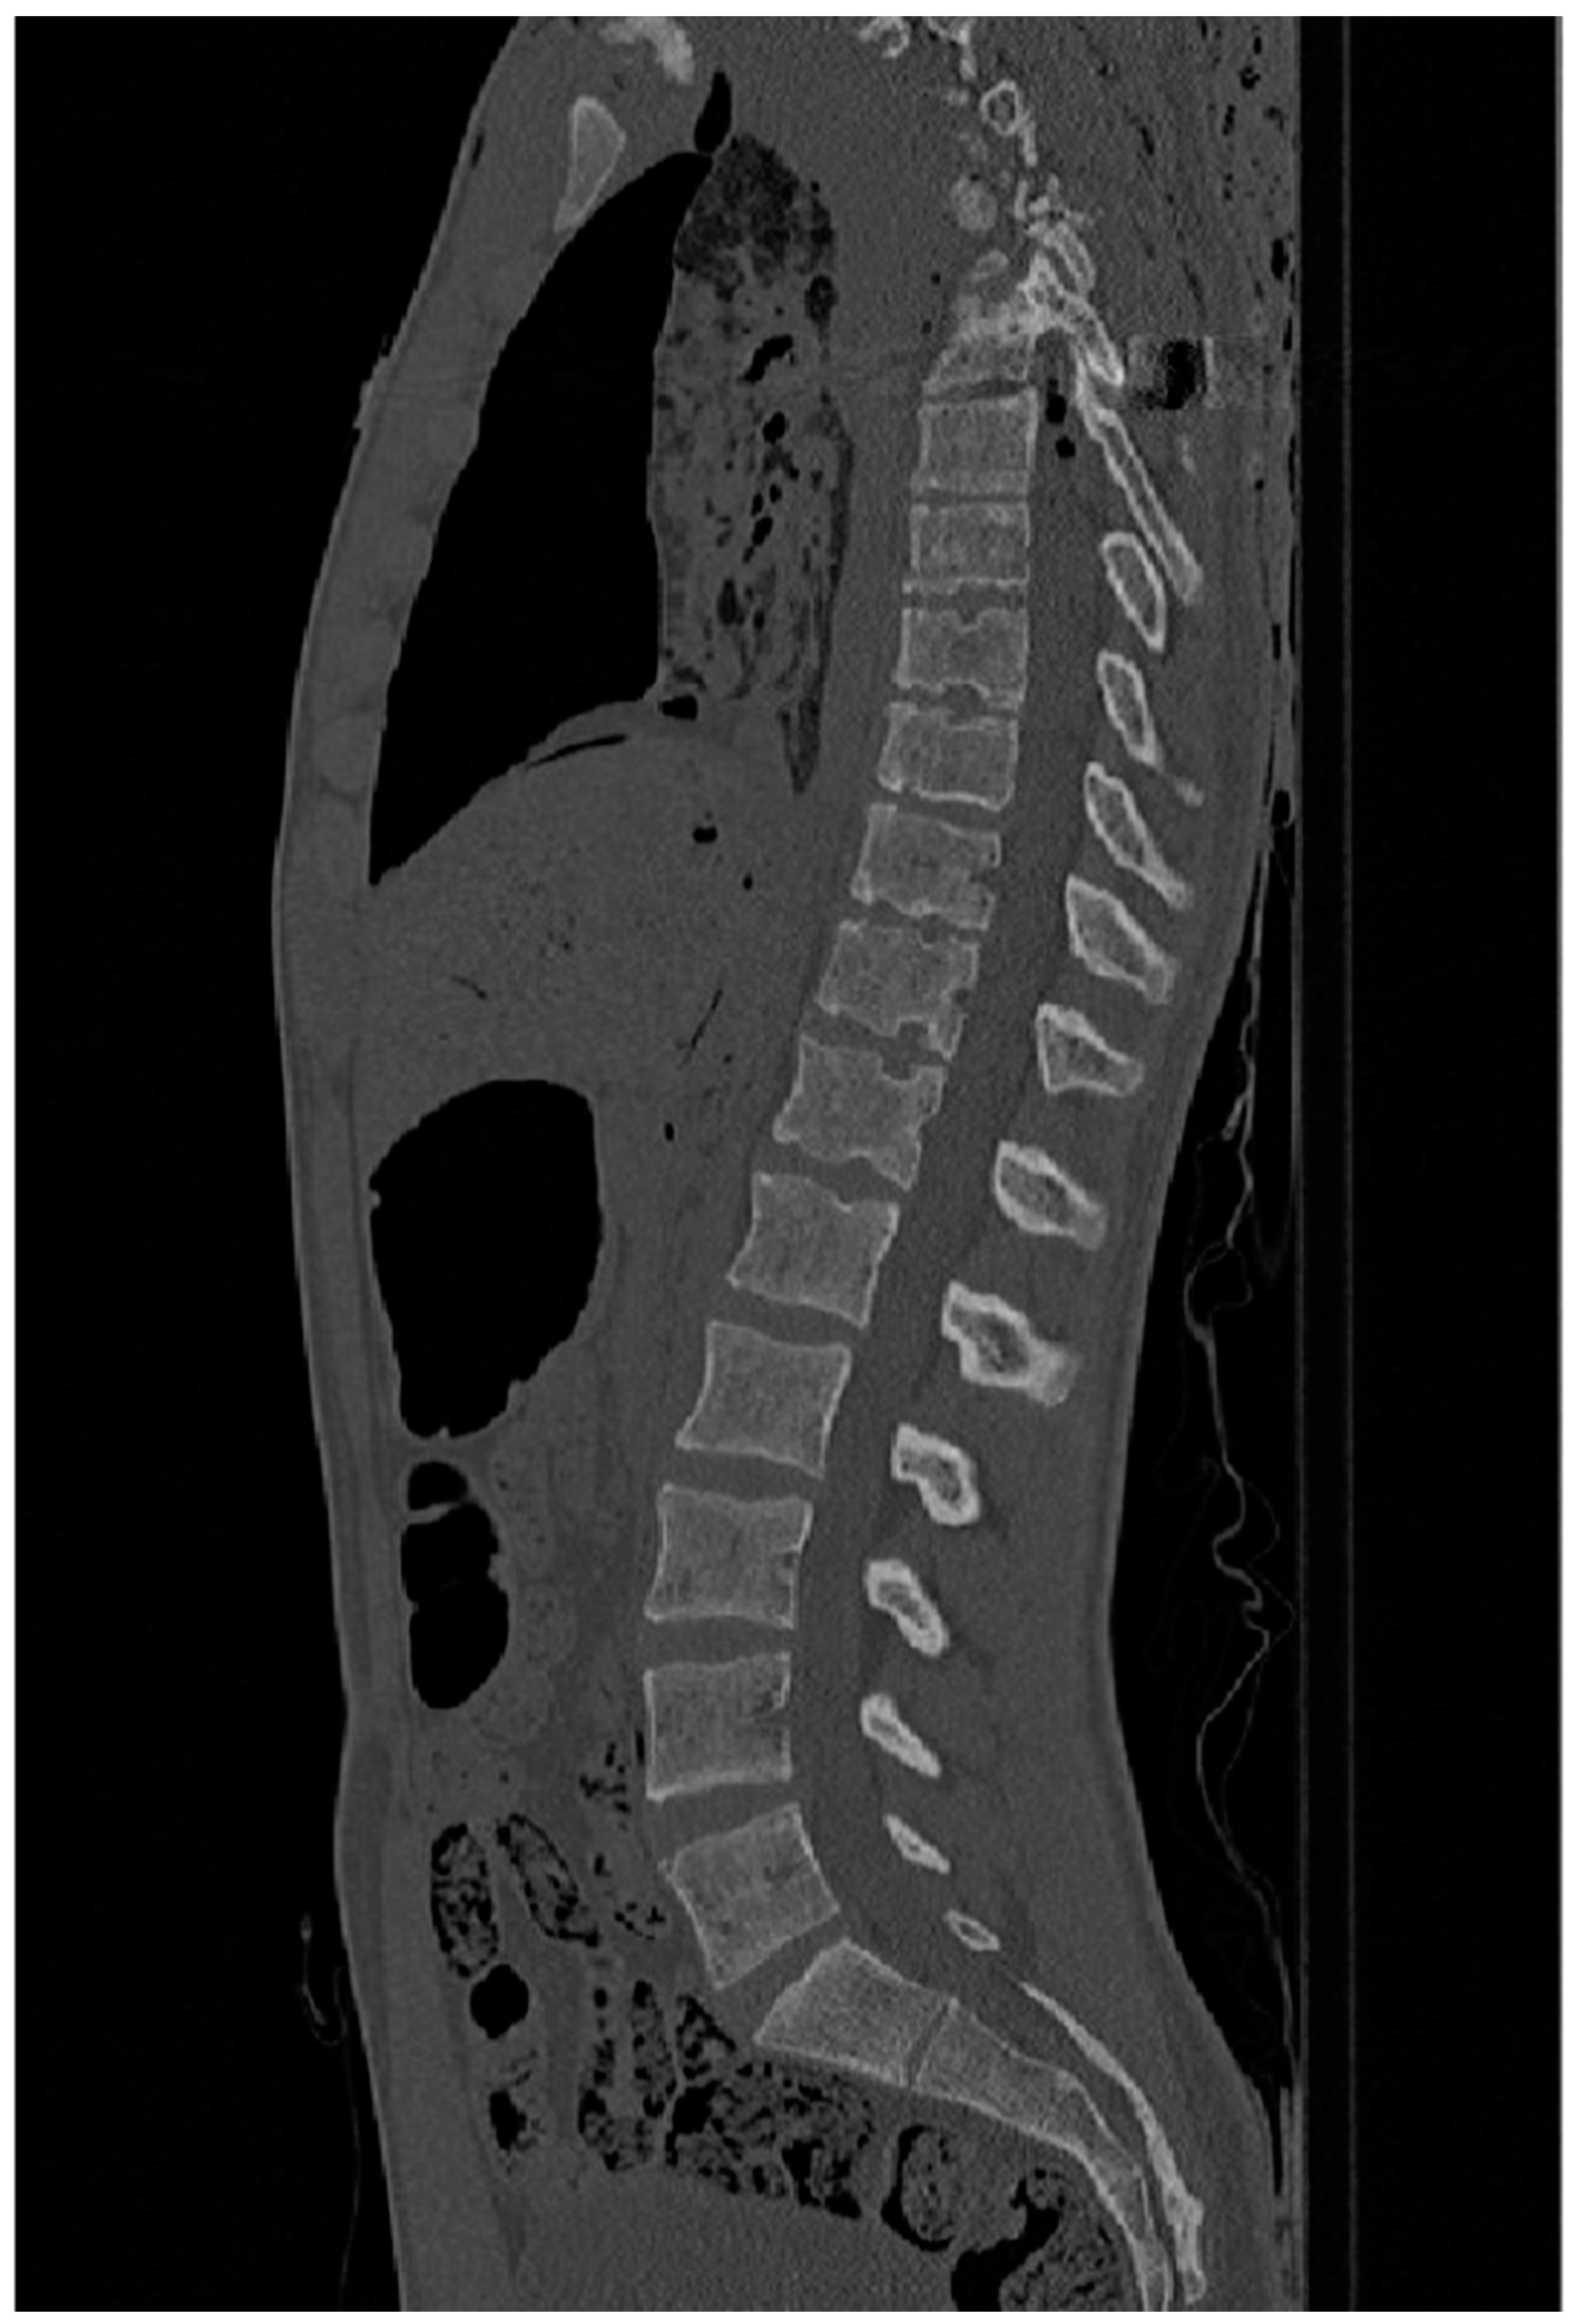

Vertebral Bone Density Variations in Scoliotic vs. Non-Scoliotic Juveniles, and Its Implications for Schmorl’s Node Development: A CT-Based Analysis Using the New Mexico Decedent Image Database

2.2. Methods